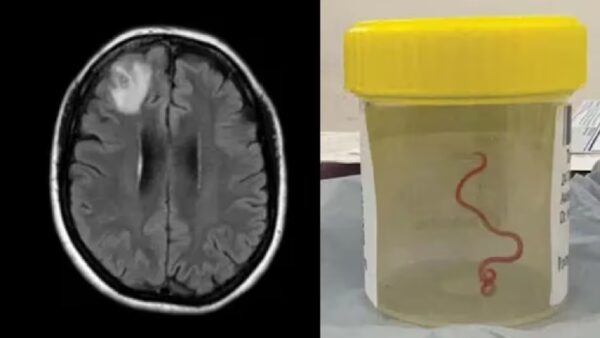

गेल्या 2021 पासून महिलेवर उपचार सुरु होते. महिलेला न्युमोनिआ, पोटदूखी, जुलाब, कोरडा खोकला, ताप आणि रात्री घाम येणे अशी सर्व लक्षणे दिसत होती. त्यानुसार डॉक्टरांनी तिला स्टेरॉईड आणि इतर औषधे देऊन तिचा उपचार सुरु केला होता. या उपचारा दरम्यान 2022 ला महिलेमध्ये डिप्रेशन आणि स्मृतिभ्रंशची लक्षणेही दिसू लागली. त्यामुळे डॉक्टरांनी तिला मेंदूचे एमआरआय स्कॅन करून सर्जरीचा सल्ला दिला होता. मात्र रिपोर्टमध्ये महिलेच्या मेंदूत किडा सापडल्याची धक्कादायक बाब समोर आली होती.

डॉक्टरांनी दिलेल्या माहितीनूसार, महिलेच्या डोक्यात आढळून आलेला किडा 3 इंच लांब, चमकदार लाल रंगाचा आहे. या किड्याला पॅरासाईट राउडवॉर्म म्हणतात. तर शास्त्रज्ञांमध्ये या किड्याला ओफिडास्कॅरिस रॉबर्टसी म्हणून ओळखले जाते. ही प्रजाती सापांमध्ये आढळते. राउंडवर्मचा हा विशिष्ट प्रकार कार्पेट पायथन्स (अजरग) मध्ये आढळतो,ही एक मोठी प्रजाती आहे. हे ऑस्ट्रेलिया, इंडोनेशिया आणि पापुआ न्यू गिनीमध्ये आढळतो.